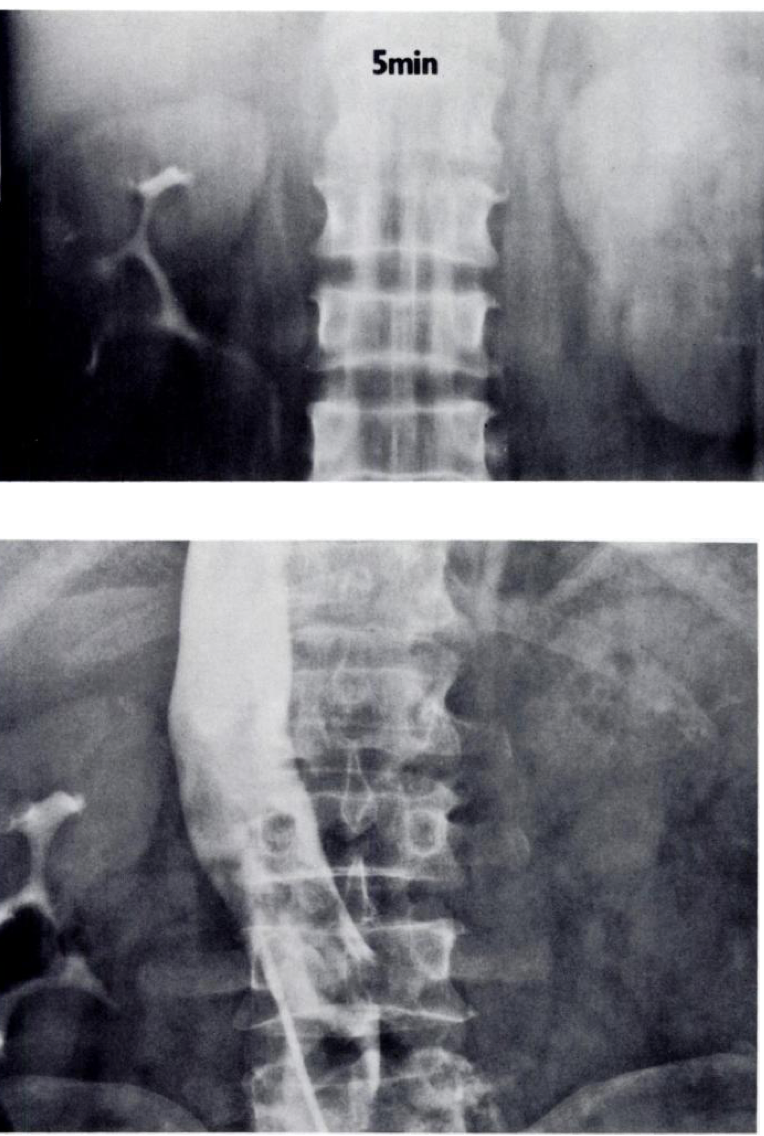

What are the signs of RVT on IVP?

What sign is this?

Delayed nephrogram

IVP: